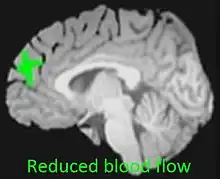

| Reduced blood flow in prefrontal cortex of adolescent cannabis users[1] | |